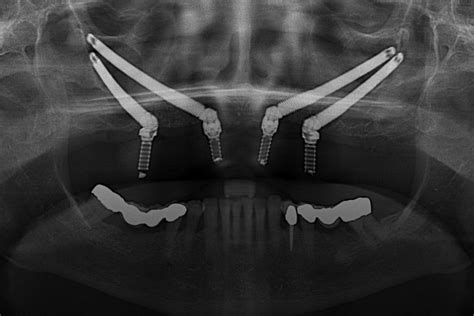

Implantes Cigomáticos

Los implantes cigomáticos representan una de las innovaciones más sorprendentes en odontología, especialmente diseñados para aquellos pacientes que presentan una cantidad insuficiente de hueso en la mandíbula.

Los implantes cigomáticos se utilizan en pacientes con una cantidad insuficiente de hueso en la mandíbula, ya que se anclan en el hueso del pómulo.

- Anclaje en el hueso cigomático: A diferencia de los implantes tradicionales, que se fijan en el hueso alveolar, los implantes cigomáticos se colocan en el pómulo, una zona con mayor densidad ósea.

- Técnica quirúrgica especializada: La colocación de estos implantes requiere una alta especialización y precisión en cirugía maxilofacial.